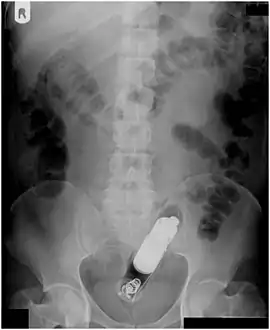

| A foreign body - in this case a swallowed toothbrush - located in the stomach cavity by using an endoscope. | |

Abdominal X-ray showing small packages of cocaine swallowed by a trafficker.